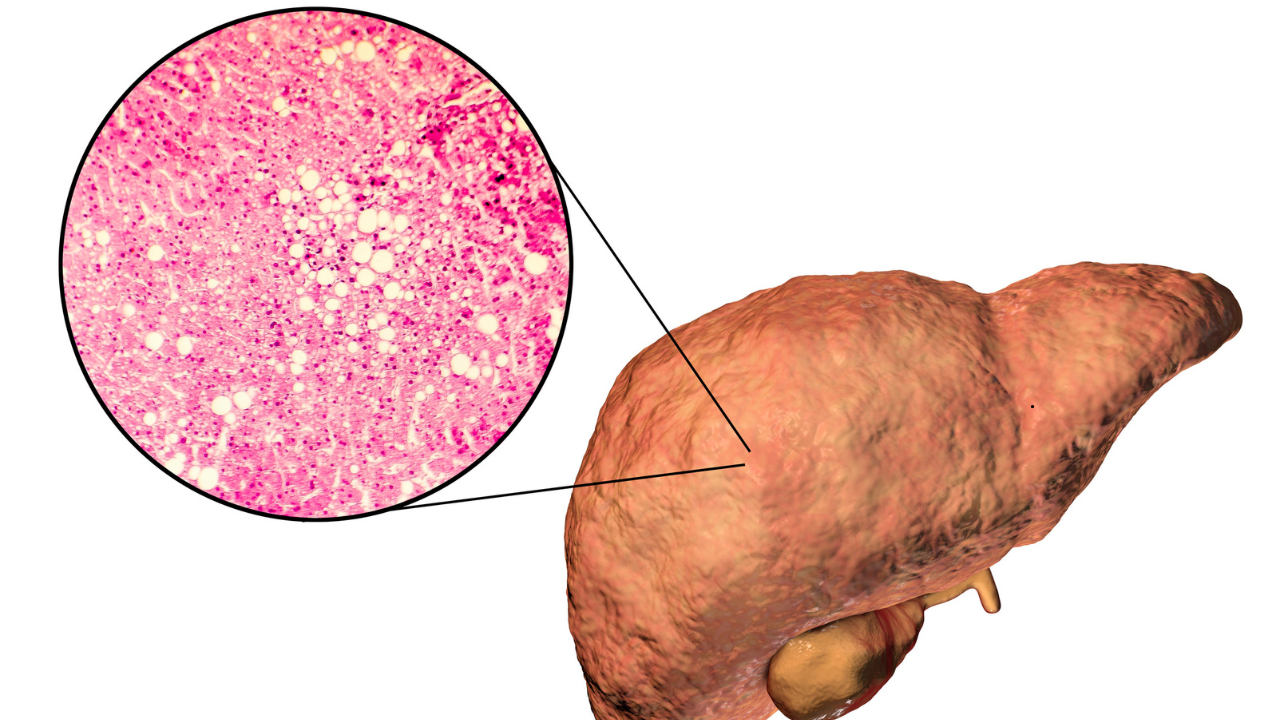

Fatty liver disease and insulin resistance often go hand in hand. It is almost like a vicious cycle. What actually happens is when the fat builds up in the liver, it interferes with the body' ability to use insulin effectively. This then triggers insulin resistance, which could fuel fat accumulation, inflammation, and then lead to liver damage. This for a long time could lead to nonalcoholic steatohepatitis (NASH), which is a severe form of fatty liver disease marked by liver inflammation and scarring. Many experts, including diabetologist Dr Brijmohan Arora has pointed that there could be certain visible changes in your body that could help you detect the early signs of NASH, without having to take a blood test. What Are The Signs You Should Not Ignore?As per the doctor, who has over 24 years of experience and practices in Dwarka. He posted a video on Instagram titled ;How to detect a fatty liver without blood tests'. The signs he says include:Excessive visceral fat — a hard, protruding belly or “belly paunch.”Skin tags: small, soft growths on the neck or armpits.Red or purple lines on the legs, especially near the ankles.A puffy or rounded face with less visible cheekbones.High blood pressure (readings above 140 mmHg).These signs, he explained, can act as “clinical clues” for doctors, especially when patients refuse blood tests.If You Have A Belly Paunch, It Is A Dangerous SignDr Arora shared story of one of his patients who refused to undergo blood tests and wanted to know whether his liver was healthy. "He had fatty live once and managed to reverse it." However, the patient had returned to the doctor, but refused any testing, this is when the doctor conducted a full physical examination to assess him. "If your stomach is very protruding and feels hard, it means fat has accumulated around and inside your organs. That is visceral fat. This is a strong indicator of fatty liver." He further added, "If you notice small warts or moles on your neck or armpits, these skin tags are often the number one sign of insulin resistance."Are There Other Warning Signs Of Insulin Resistance?Dr Arora also pointed out several other important indicators, including red or purple lines on the feet. He said, "If you see small red or purple lines on your feet, especially near your ankles, it may be a sign of insulin resistance. A puffy face, where your cheekbones are no longer visible, is another common clue." He also noted that high blood pressure could be one of the most serious warning signs. "If your blood pressure is consistently above 140 or 145, that is quite dangerous. It is one of the most important clinical features of insulin resistance." View this post on Instagram A post shared by Dr Brijmohan Arora | Diabetologist Dwarka (@drbrijmohanarora)]]> Why Is Early Detection Important?Fatty liver disease and insulin resistance are not just metabolic issues, they can set the stage for type 2 diabetes, cardiovascular disease, and severe liver conditions like NASH. Detecting these early signs can help you take timely steps through diet, exercise, and medical consultation.Experts recommend maintaining a healthy weight, managing blood sugar, and limiting processed foods and alcohol to protect your liver. Note: This piece is based on an Instagram post by Dr Arora. Health And Me does not, in any way, promote diagnosis without proper medical testing.